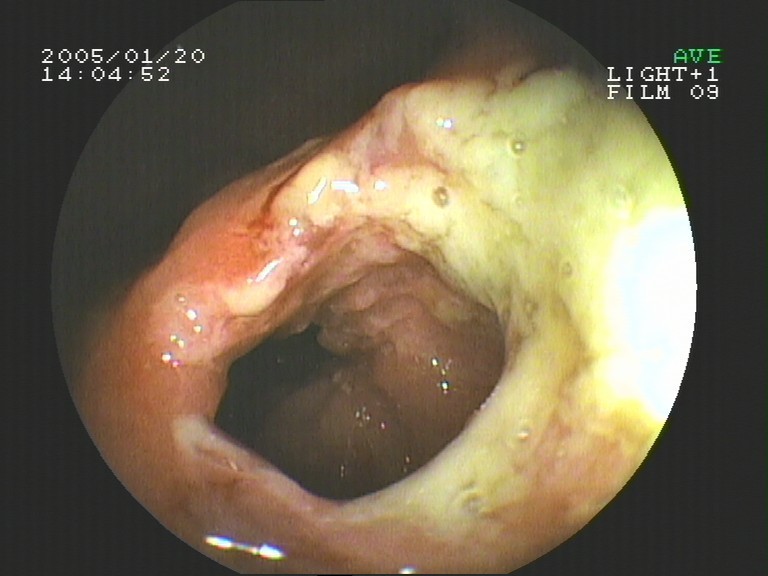

Coloskopie - pseudomembranöse Colitis (bakterielle Dickdarmentzündung)